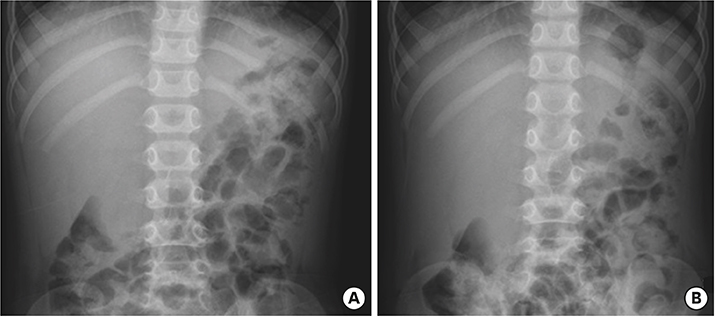

On the first day after admission, he received 2 g/kg IVIG and 50 mg/kg/day aspirin, following which his fever subsided and no further IVIG treatment was needed. His first echocardiography showed myocarditis (ejection fraction [EF], 45%) and mild ectasia of left main coronary artery (3.2–3.4 mm in diameter). On the second day after his admission, echocardiography (second follow-up) showed improved mild myocarditis (EF, 55%), improved ectasia of left main coronary artery (2.7–2.8 mm in diameter), and severe GB distension (8.9×4.6 cm in size), which possibly indicated GB hydrops (Fig. 2A). On the fourth day after his admission, although he had no fever and exhibited improvements in KD symptoms (i.e., eye injection, rash on abdomen, and cervical lymphadenopathy), he still complained of abdominal pain, distension, and tenderness of the RUQ. Follow-up laboratory findings were improved: neutrophilic leukocytosis (6,130 cells/mm3, with 33% neutrophils); decreased CRP (4.4 mg/dL), BNP (347 pg/mL), AST (40 U/L), and ALT (72 U/L); and improved hyperbilirubinemia (total bilirubin, 0.7 mg/dL). Echocardiography (third follow-up) showed normal completely improved carditis and still severe GB distension (10.2×5.5 cm in size) (Fig. 2B). Abdominal ultrasonography (US) was performed, which showed a markedly distended GB without stone, sludge, or wall thickening as well as normal bile ducts and liver morphology, which confirmed GB hydrops (Fig. 3A). On the sixth day after his admission, although his signs of KD had nearly disappeared, he still complained of abdominal discomfort, which had been moderately improving. The second follow-up abdominal US revealed a no notable change in GB distension compared to previous sonographic findings (Fig. 3B). An abdominal computed tomography (CT) scan was also obtained to exclude other hepatobiliary abnormalities, which showed similar findings as sonography, including a marked dilatation of the GB (8.0×5.5 cm in size) without stone, sludge, or wall thickening as well as normal bile ducts and liver morphology (Fig. 4). No complications necessitating surgical intervention had occurred and he was discharged 7 days after admission with only mild tenderness on the right upper-mid quadrant.

Echocardiography showed severe gallbladder distension (A) 8.9×4.6 cm in size and (B) 10.2×5.5 cm in size.

Fig. 2 Echocardiography showed severe gallbladder distension (A) 8.9×4.6 cm in size and (B) 10.2×5.5 cm in size.